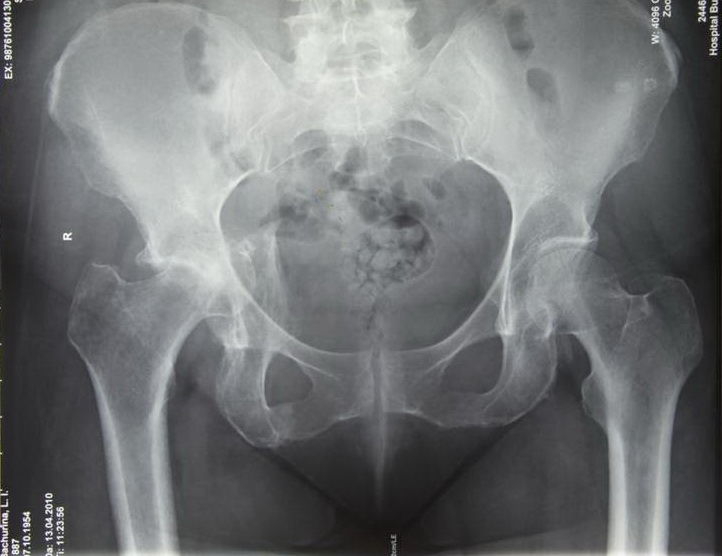

На сегодняшний день общепризнано, что эндопротезирование тазобедренного и коленного суставов является единственным эффективным методом лечения при разрушении суставного хряща и позволяет избавит пациента от боли и вернуть его к активной жизни. В мире ежегодно выполняется более полутора миллионов таких операций. Современные эндопротезы служат десятки лет и позволяют жить полноценной жизнью даже молодым и активным пациентам, а в случае, если эндопротез всё же износился, его можно заменить на более сложный и продолжать пользоваться всеми благами жизни.

Ортопедическое отделение Главного военного клинического госпиталя им. акад. Н.Н.Бурденко занимается вопросами эндопротезирования крупных суставов более 30 лет. Мы прошли весь тернистый путь проб и ошибок в освоении этой специальности, познали горечь неудач и радость успеха. В отделении разработаны и запатентованы: уникальная методика двухэтапного эндопротезирования тазобедренных суставов, новые способы костнопластического замещения значительных дефектов вертлужной впадины при ревизионных операциях.

В последние годы мы активно занимаемся проблемой эндопротезирования тазобедренного сустава у молодых пациентов, в том числе при врождённой патологии (дисплазии) используя при этом новейшие высококачественные долговечные эндопротезы.